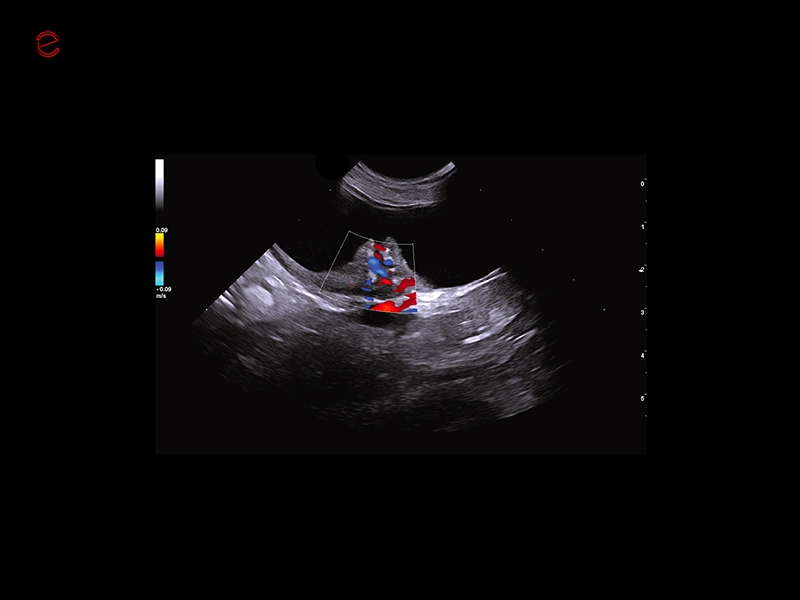

HIGH-RESOLUTION IMAGING IN ALL APPLICATIONS

Unmatched vision

Herons have exceptional eyesight, enabling them to detect subtle movements even in challenging conditions, making them highly effective hunters. Similarly, MyLab™Heron offers incredibly detailed and high-resolution imaging, in superficial areas as well as in deeper ones, thanks to the wide range of probes. All this makes it possible to scan from the smallest to the biggest animals in all applications covering general imaging, cardiology, musculoskeletal, reproduction, and ensuring unmatched clarity in all your examinations.